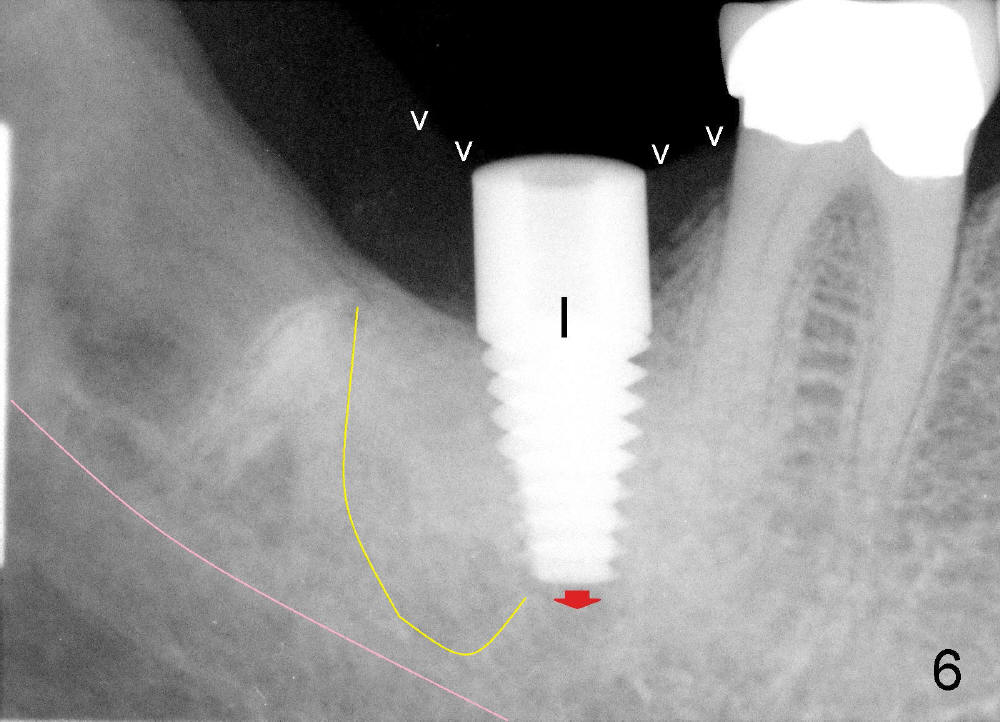

A postop PA is taken immediately after 6x14 mm tapered implant is placed (Fig.6 I). The top of the implant remains at the gingival level (white arrowheads). The implant is later further torqued down about 0.5 mm (red arrow).

Mrs. Hwang in her sixties has had periodontal disease in her lower right 2nd molar (Fig.1 *). Three years later, both the 2nd and 3rd molars are extracted (Fig.2; pink: the upper border of the inferior alveolar canal). Four months after extraction, the patient returns for implant placement at the site of #31 (Fig.3, 4). The socket of the 2nd molar is outlined in yellow in Fig.3.

An intraop PA is taken with 4x14mm tapered drill in place (Fig.5 D). It appears that the osteotomy is deviated to the mesial portion of the healed socket (yellow outline). While the top of drill is at the gingival level (arrowheads), the tip of drill is 3.34 mm from the inferior alveolar nerve.